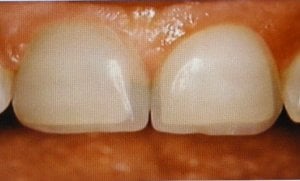

Zirkonyum ışık geçirmesi, metal alerji sorunu yaratmaması ve diş renginde olması nedeni ile en çok ...

Estetik Diş Hekimliğinde Lamine Dişler nasıl yapılır, ağızdaki dişlere uygulama aşamaları nelerdir? Lamina ne kadar ...